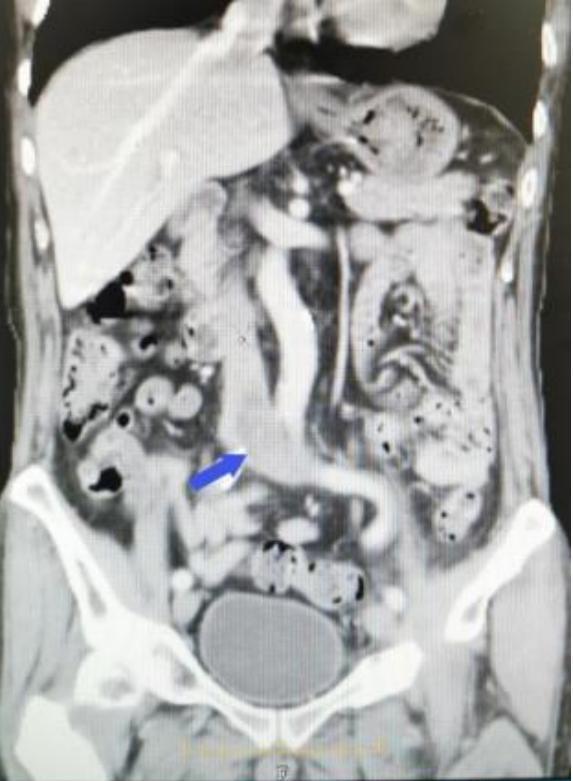

(▲术前彭先生CT影像资料,蓝色箭头所指为下腔静脉内血栓)

情况危急!血栓已经扩散到下腔静脉内,下腔静脉内的血栓也随时有可能脱落跑到肺内加重肺栓塞,甚至导致猝死的可能。急诊手术指征明确。